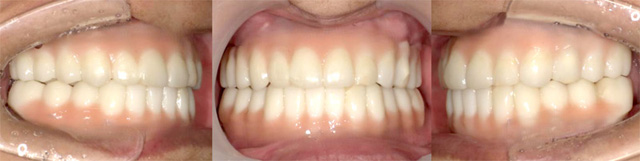

オールオン4の治療例:1

治療前

治療後

オールオン4の治療例:2